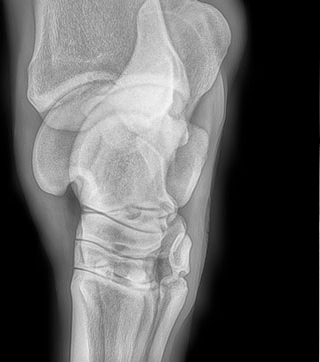

Radiología

Contamos con el equipo de radiología digital inalámbrico más avanzado del país, el cual permite obtener las mejores imágenes en el acto y compartirlas vía mail. Realiza radiografías de miembros, columna, cabeza, cuello y hombro.